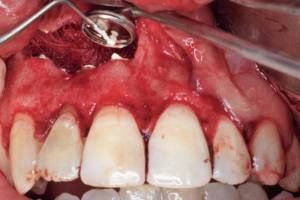

· Imagen 1, leer más...

La cirugía periapical es un procedimiento quirúrgico que tiene como objetivo la remoción de un granuloma o quiste apical con la consiguiente extirpación de la porción apical del diente afectado (apicetomía). En dicha imagen se observa el ápice seccionado y el alveolo remanente que deja la extirpación del tejido infeccioso así como el relleno con MTA del tercio más apical de la raíz del diente endodonciado.